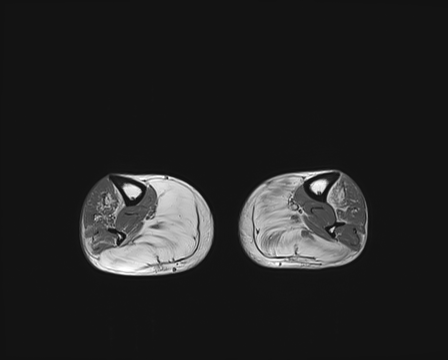

We chose the Fusion_Gate method for our application-grounded evaluation because it achieved the highest scores, albeit modest, in our functionally-grounded evaluation. Figure 7 presents all five distal myopathy cases side by side with their reference masks and the corresponding Fusion_Gate saliency maps, providing a direct visual comparison of true pathology versus model-identified regions. After converting each HCP’s annotations into binary masks, we computed the coherence between those masks and the Fusion_Gate saliency maps (Table 7). The large spread in RMA and RRA values demonstrates that even minor discrepancies in the ground truth mask can dramatically alter coherence scores, emphasizing the critical need for highly accurate, consensus ground truth annotations when using coherence as an interpretability metric. We then assessed each HCP’s overall annotation accuracy by RMA¯\overline{\mathrm{RMA}}over¯ start_ARG roman_RMA end_ARG and RRA¯\overline{\mathrm{RRA}}over¯ start_ARG roman_RRA end_ARG against the reference masks (first column of Table 8). RMA¯\overline{\mathrm{RMA}}over¯ start_ARG roman_RMA end_ARG indicates that HCPs reliably identify the general signal alteration regions, but their consistently lower RRA¯\overline{\mathrm{RRA}}over¯ start_ARG roman_RRA end_ARG confirms they lack the fine-grained precision of the expert in isolating the most critical subregions. Notably, when we compare these human baselines to the Fusion_Gate’s mean coherence scores (Table 5), the method’s RRA¯\overline{\mathrm{RRA}}over¯ start_ARG roman_RRA end_ARG surpasses that of all but two HCPs. In other words, the attention mechanism could faithfully highlights the single most important pixel than most individual annotators. Lastly, the comparatively low RMA¯\overline{\mathrm{RMA}}over¯ start_ARG roman_RMA end_ARG and RRA¯\overline{\mathrm{RRA}}over¯ start_ARG roman_RRA end_ARG values in the second column of Table 8, which quantify how well the Fusion_Gate saliency maps align with each HCP’s own mask, reveal that even our best interpretability method still falls short of expert-level delineation. In other words, although attention-based saliency can highlight broadly relevant regions, it does not yet match the clinical precision of HCPs’ annotators. This gap underscores that, despite promising advances, more work is needed before automated explanations can achieve the same fidelity as experienced radiologists.

Refer to caption

(a) Image 1

(b) Ground truth Mask 1

(c) Saliency Map 1

(d) Image 2

(e) Ground truth Mask 2

(f) Saliency Map 2

(g) Image 3

(h) Ground truth Mask 3

(i) Saliency Map 3

(j) Image 4

(k) Ground truth Mask 4

(l) Saliency Map 4

(m) Image 5

(n) Ground truth Mask 5

(o) Saliency Map 5

Figure 7: Image instances of the distal myopathy dataset with their corresponding reference masks and saliency maps.